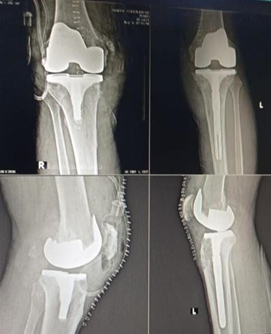

Figure 2. Post op X-ray.

TKA was performed (tibial preparation using extramedullary jig, femoral preparation using intramedullary jig.) on left side we had to insert stem. Stem was added in order to improve mechanical stability and to shear stress and decrease micromotion at distal Femur. and on right side conventional method was applied and TKA was done in routine fashion.

The patient was followed up at two-week and monthly intervals till one-year follow up. Physiotherapy commenced at six weeks post-surgery. At two months, he had mild effusion and pain in the left knee, but radiographs were unremarkable. Bilateral knee range of motion was 0–100°.